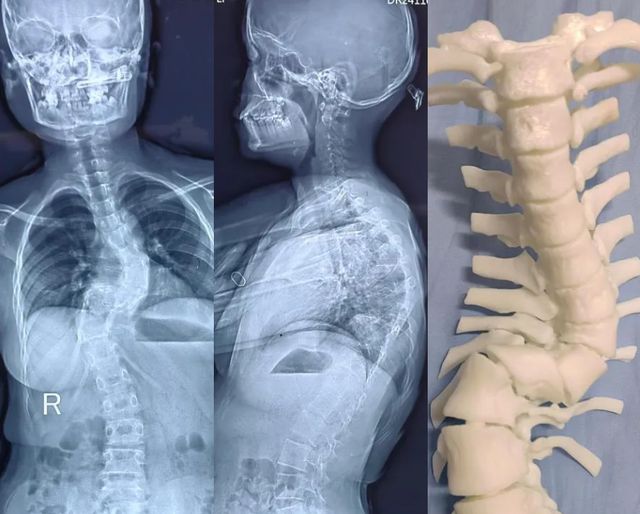

经西安市红会医院首席专家、脊柱病医院郝定均院长及侧弯与疼痛病区主任惠华团队系统检查,确诊小莉罹患神经纤维瘤病Ⅰ型(NF1)合并胸椎Z型重度侧凸。超过6处直径>5mm的牛奶咖啡斑,或腋窝“雀斑样”色素沉着;影像显示其椎体旋转畸形严重,存在典型"铅笔样"肋骨改变及椎弓根变薄特征。"这类患者30%伴随椎管内肿瘤,手术难度大,犹如在神经丛林中排雷。"惠华主任解释。

面对脆弱变形的脊柱结构,医疗团队制定四步矫形方案:先期采用halo-重力牵引渐进拉伸脊柱;术中借助天玑骨科机器人实现畸形椎体毫米级精准置钉;在神经电生理实时监护下完成高难度截骨松解;最终安装矫形棒对侧凸进行矫正,在顶椎区连接卫星棒予以加固。整个手术团队犹如在刀尖起舞,成功规避神经损伤风险。